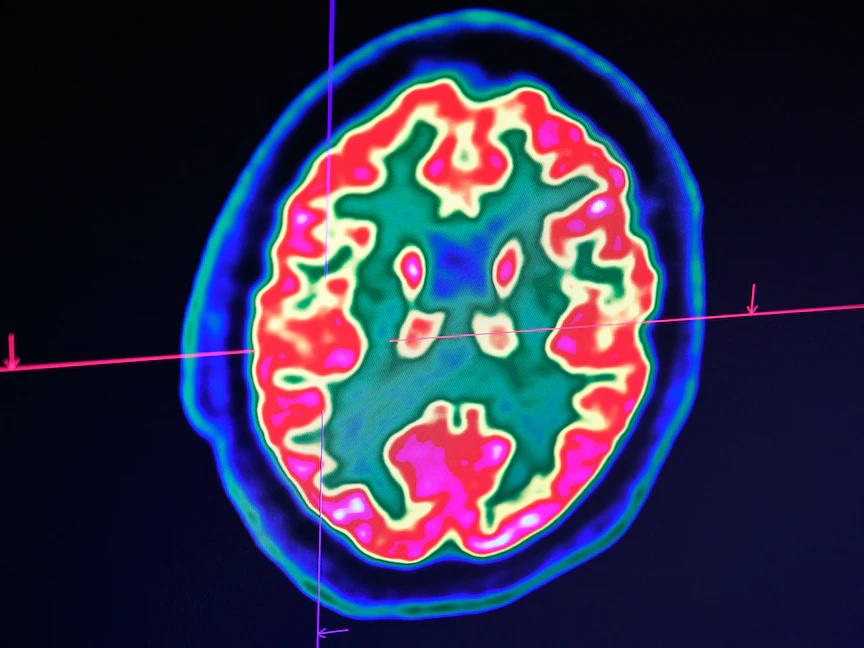

أفادت دراسة حديثة بأن العيش في المناطق ذات الخيارات الواسعة للوجبات السريعة، والتي وصفتها بـ"مستنقعات الطعام"، قد يؤدي إلى زيادة خطر الإصابة بالسكتة الدماغية بين أولئك الذين تتجاوز أعمارهم 50 عاماً.

وأشارت الدراسة التي ستُقدم في "المؤتمر الدولي للسكتة الدماغية" في الفترة ما بين 8 إلى 10 فبراير الجاري في دالاس الأميركية، إلى أن من تتجاوز أعمارهم 50 عاماً، وكانوا يسكنون قرب أماكن تقدم وجبات سريعة وبيئة غذائية غير صحية تُعرف بـ"مستنقعات الطعام"، أكثر عرضة للإصابة بالسكتة الدماغية، مقارنة بمن عاشوا في مناطق بها عدد أقل من خيارات بيع التجزئة والوجبات السريعة.

ويؤثر النظام الغذائي غير الصحي سلباً على ضغط الدم، ونسبة الجلوكوز في الدم، ومستويات الكوليسترول، التي تزيد من خطر الإصابة بالسكتة الدماغية.